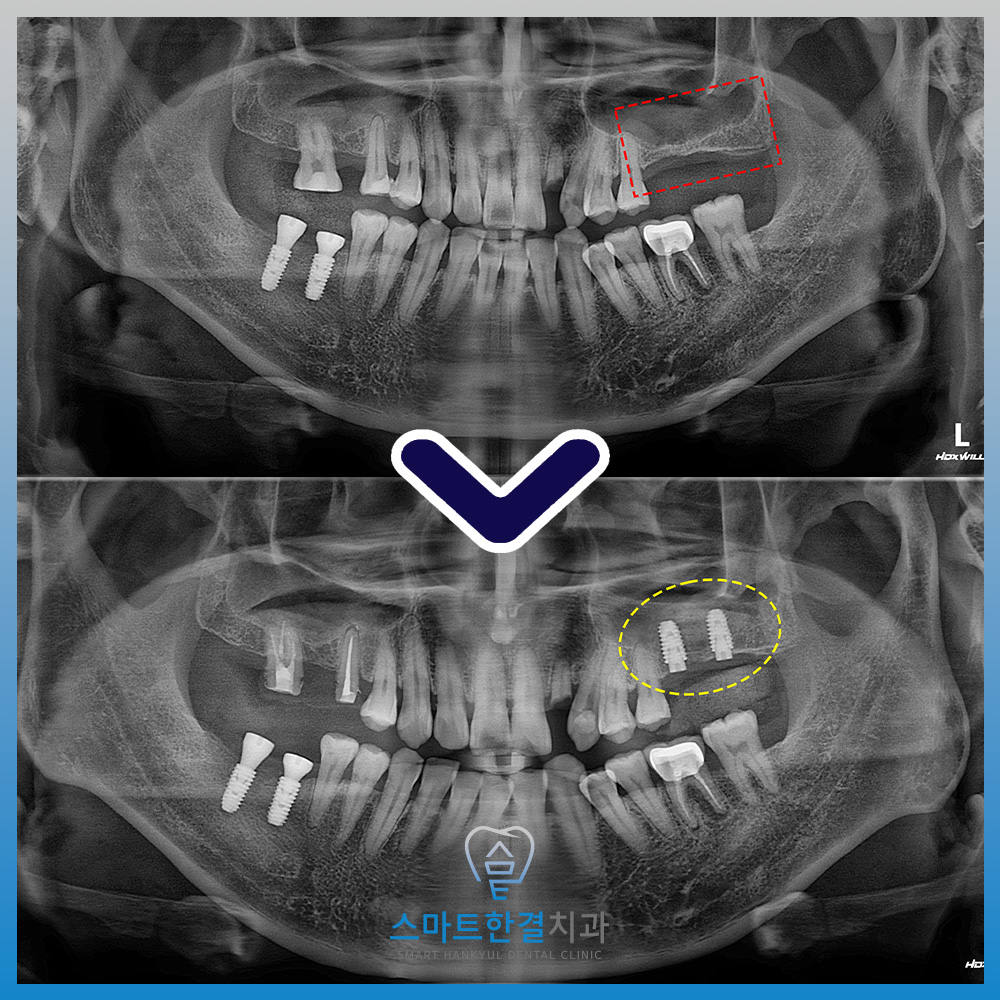

파노라마를 촬영해 확인해 보니,

왼쪽 위 큰 어금니의 상실로 인해

양측으로 식사하기 힘든 상황이었어요.

또한 치아가 오랫동안

없는 상태로 방치되면서,

치조골이 점차 흡수·소실되어

뼈의 높이가 부족한 상황이 되었어요.

이로 인해 임플란트만

바로 식립하기는 어려웠고,

상악동거상술을 통해 부족한 뼈를

보강하는 과정이 필요했는데요.

그래서 본원에서는 상악동거상술을 진행하여

충분한 뼈의 공간을 확보한 뒤,

안정적으로 임플란트를 식립할 수 있도록

계획을 수립했답니다.

측방으로 접근하여

잇몸뼈를 조심스럽게 열고,

상악동 막을 들어 올린 뒤

그 공간에 인공뼈를 이식하는

과정을 진행했어요.

이를 통해 임플란트를

안정적으로 식립 할 수 있는

충분한 골량을 확보할 수 있었어요.

알려드린 주의사항을 잘 지켜주셔서

지금까지 특별한 이상 없이

뼈가 안정적으로 자리 잡고 있어요.^^